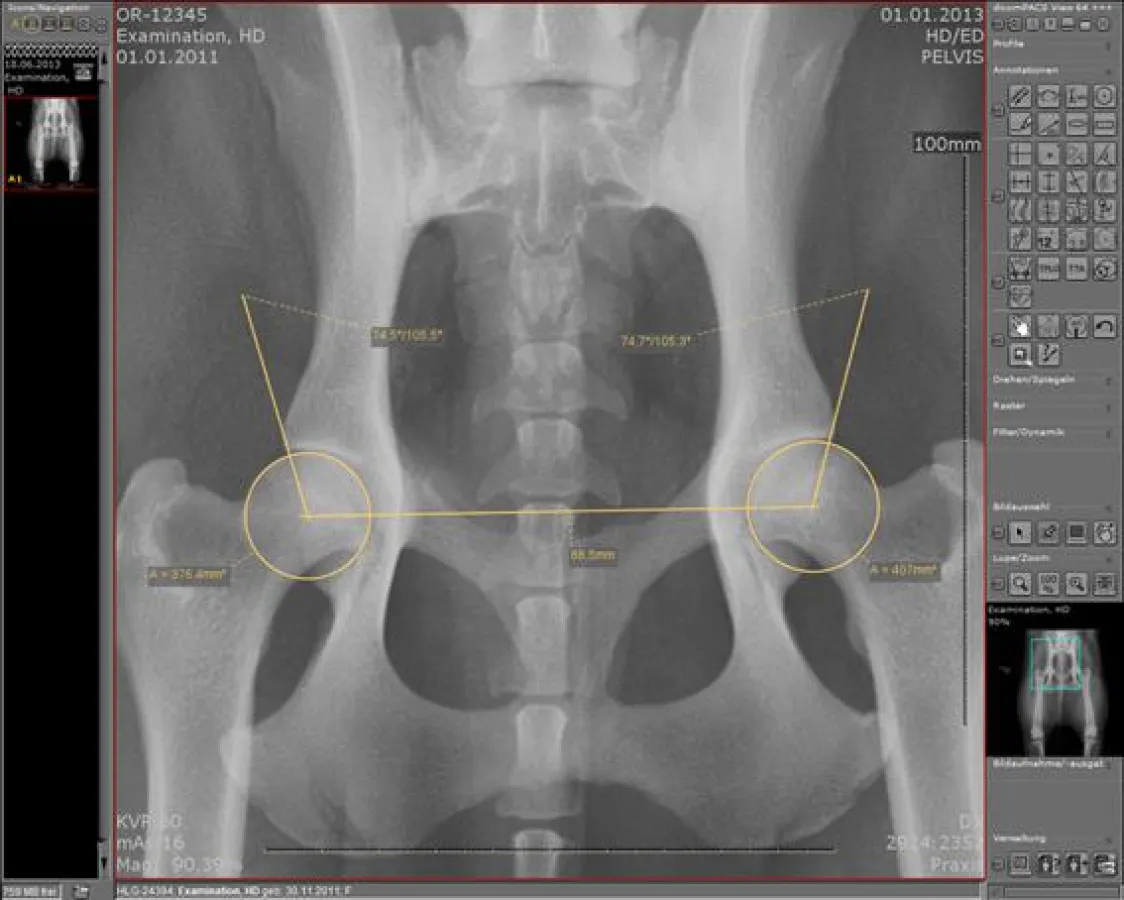

(openPR) Die Ludwig-Maximilians-Universität (LMU) München ist eine der führenden Universitäten in Europa mit einer über 500-jährigen Tradition. Die Studienmöglichkeiten mit rund 150 Angeboten nehmen jährlich rund 48.000 Studierende in Anspruch. Der chirurgische Tierärztliche Fachbereich, einer der 18 Fakultäten der LMU, nutzt nun an über 30 Arbeitsplätzen das inhouse konzipierte Bildmanagementsystem dicomPACS®vet der Oehm und Rehbein GmbH zur täglichen Diagnostik von Kleintieren. Tierbesitzer erhalten hier für ihre kleinen Schützlinge sowohl ambulant, als auch stationär Betreuungsleistungen nach höchsten wissenschaftlichen Standards. Mit der Ablösung des alten Bildverwaltungssystems durch dicomPACS®vet im Zentrum für Klinische Tiermedizin (Chirurgische und Gynäkologische Kleintierklinik) unter der Leitung des Klinikvorstandes Prof. Dr. med.vet. Andrea Meyer-Lindenberg verfügen die Mitarbeiter über ein einfach zu bedienendes, durchdachtes Instrument für das tägliche Stellen von Diagnosen. Neben der großen Funktionalität sind es insbesondere die spezifischen veterinärmedizinischen Tools, die Prof. Dr. med.vet. Andrea Meyer-Lindenberg überzeugen. Dazu zählen u. a. die HD-Vermessung inkl. Bestimmung des Norbergwinkels, die Prothesenplanung, Vermessungshilfe TTA und TPLO sowie das Distraktions-Index-Tool. Die Software umfasst die Akquisition, Verarbeitung, den Transfer und die Archivierung von Bildmaterial. Mit mehr als 5.000 installierten Arbeitsplätzen im In- und Ausland hat sich das System vielfach bewährt. dicomPACS®vet meistert einfache Bildverarbeitungsanforderungen genauso hervorragend wie komplexe radiologische Netzwerke (PACS).